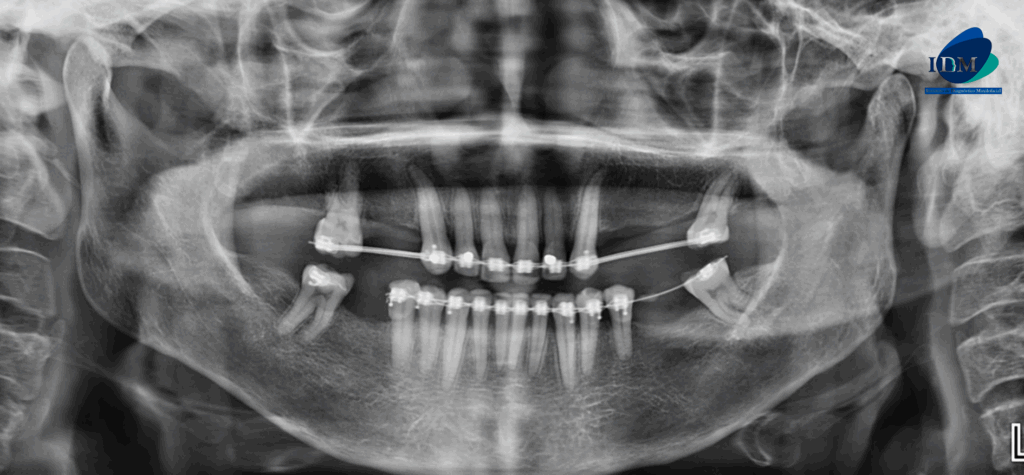

Paciente femenino de 58 años acude al Instituto de Diagnostico Maxilofacial para realizarse una tomografía para la colocación de implante dentales. A la evaluación de la radiografía panorámica se observa paciente edéntulo parcial y dispositivo de ortodoncia fija en piezas del maxilar superior e inferior, asimismo se observa la bifurcación del conducto dentario inferior del lado derecho que se extiende hacia la zona retromolar (variante anatómica)

Radiografia Panorámica